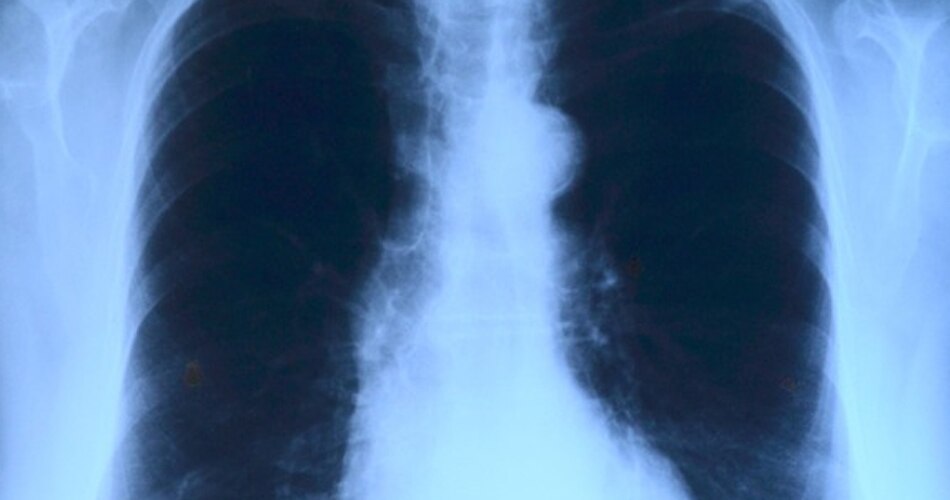

ऐसे लोगों की संख्या बढ़ती जा रही है जो स्मोकिंग ना करने के बावजूद इस कैंसर का शिकार हो रहे हैं. WHO की एक रिपोर्ट के अनुसार, लंग कैंसर के नॉन स्मोकर्स पीड़ितों की संख्या लगातार बढ़ती जा रही है और इसकी सबसे ज्यादा शिकार महिलाएं हो रही हैं.

कैंसर की बीमारी तब होती है जब शरीर में कोशिकाओं का नियंत्रण बिगड़ जाता है और वो गलत दिशाओं में बढ़ने लगती हैं. बहुत ज्यादा सिगरेट पीने से फेफड़े खराब हो जाते हैं और आसानी से कैंसर की चपेट में आ जाते हैं.

स्मोकिंग से होने वाले लंग कैंसर और नॉन स्मोकिंग लंग कैंसर में बहुत अंतर है. ये अंतर कैंसर बनाने वाली कोशिकाओं की जीन में होता है. नॉन स्मोकर्स में आमतौर पर कैंसर ईजीएफआर जीन (EGFR gene) में बदलाव की वजह से होता है.